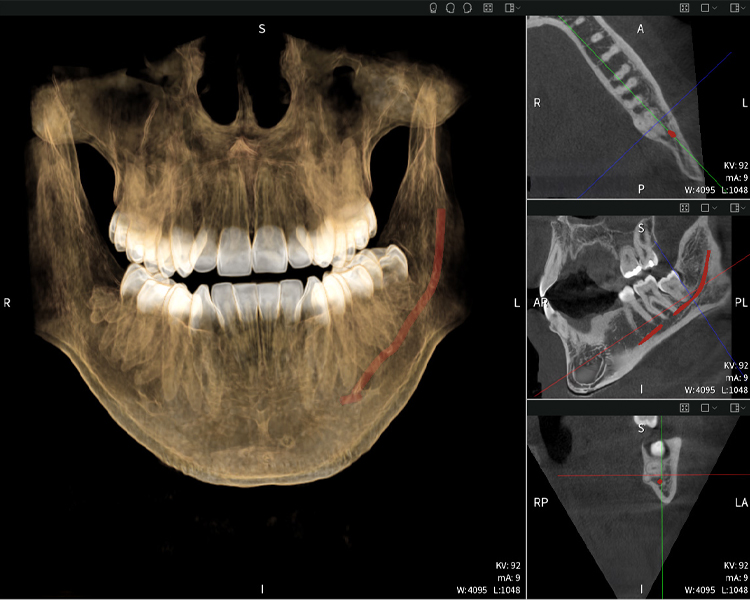

Figure d: Imaging results of Seethrough Max, in front of a black background.

Figure d

Figures b–d show various views of a 3D reconstruction of the mandible, providing a comprehensive overview of the mandibular anatomy, the position of the nerves in relation to the teeth, and allowing assessment of tooth symmetry and alignment.

Figure d shows the previously treated tooth 48, with its crown removed, and its roots left in proximity to the nerve, illustrating the high risk of nerve damage.